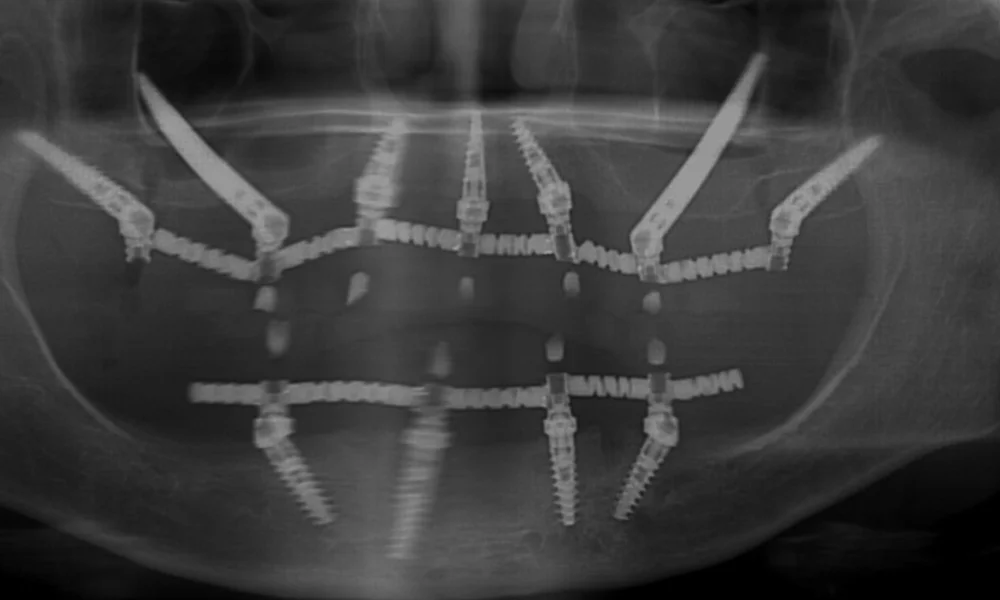

השתלת שיניים במרפאות ד"ר יגאל בלן נעשית בטיפול אחד ומבוססת על טכניקה שנקראת "העמסה מיידית", תפישה טיפולית ששינתה את ההבנה שלנו לגבי תגובת הגוף לשתלים דנטליים.

אם בעבר חשבו שצריך לבצע השתלה במספר שלבים כדי לאפשר לגוף לנוח ולהחלים אחרי כל שלב בטיפול, היום אנחנו יודעים שדווקא ריכוז של כל שלבי הטיפול לטיפול אחד קצר מקטין את הטראומה של הגוף ומשיג אחוזי הצלחה גבוהים במיוחד.